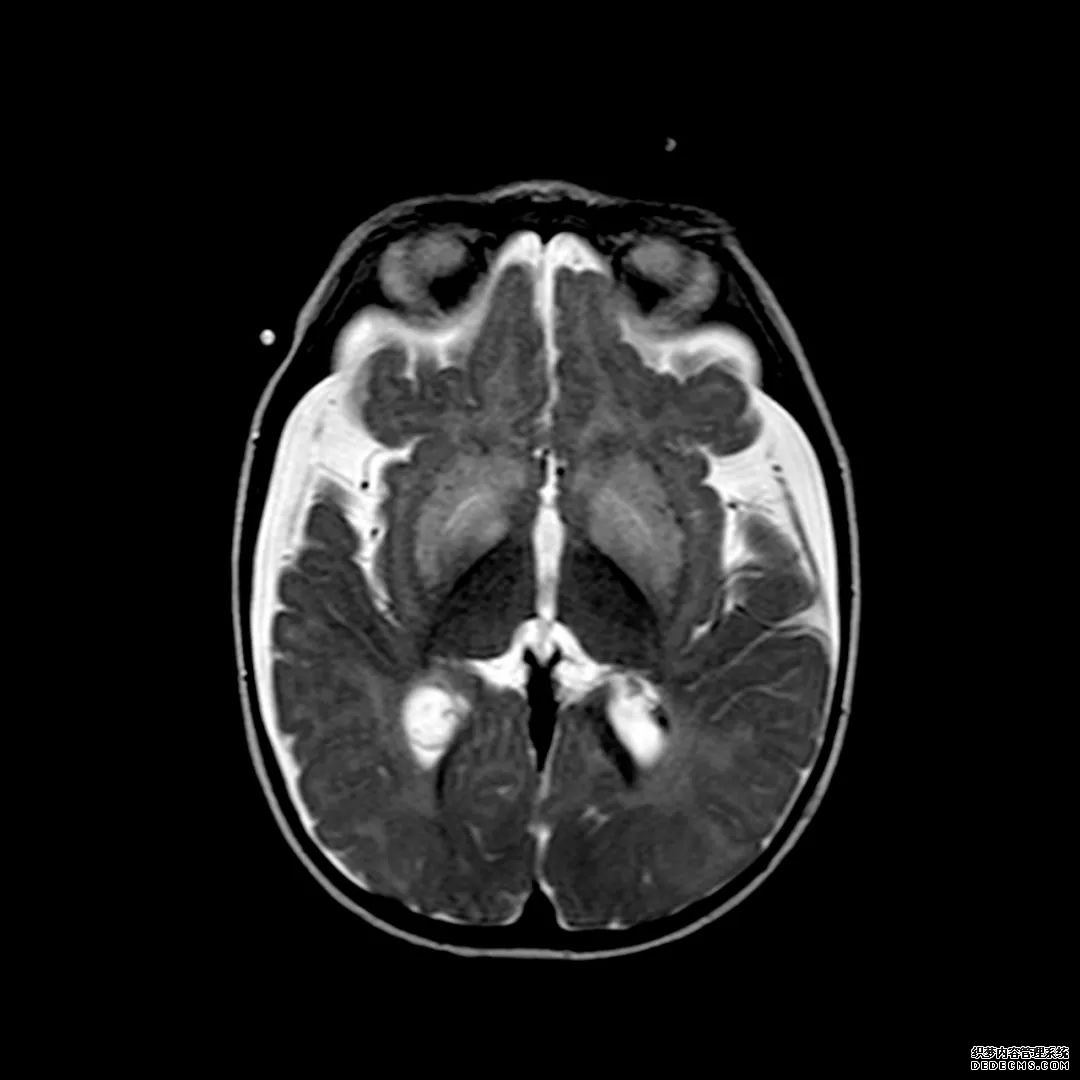

脑MRI显示尾状核、扁豆状核和脑梗头部T2/FLAIR呈双侧对称异常高信号。扩散限制涉及这些区域,其特征是扩散加权DWI(B-1000)上的高强度,ADC图上相应的减弱强度。

印象:通过将这些成像模式与临床和实验室检查结果相结合,就有可能得出低血糖性脑病。

影像影响内囊后肢、大脑皮层(特别是枕叶和岛叶)、海马和基底节区,常是双边对称性的。